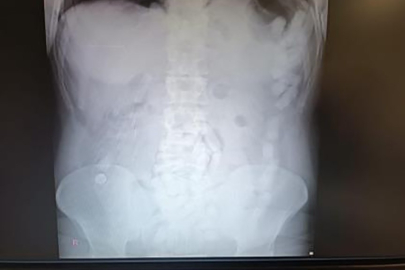

4 Mayıs 2024'te Kayseri İl Emniyet Müdürlüğü Narkotik Suçlarla Mücadele Şube Müdürlüğü ekipleri, yabancı uyruklu A.H.'nin ülkeye giriş yaparak üzerindeki uyuşturucu maddeleri Kayseri'ye getireceğini tespit etti. Şahsı takibe alan ekipler, yerini tespit ettikten sonra operasyon düzenledi. Kayseri Şehir Hastanesinde ultrason çekimi ile yapılan kontrolde şahsın midesinde çok sayıda kapsül olduğu tespit edildi. Yapılan operasyonla şahsın midesinden çıkarılan 100 adet kapsülün içerisinde 729 gram uyuşturucu madde ele geçirildi. İşlemlerinin ardından adliyeye sevk edilen şüpheli, çıkarıldığı mahkemece tutuklanarak cezaevine gönderildi.